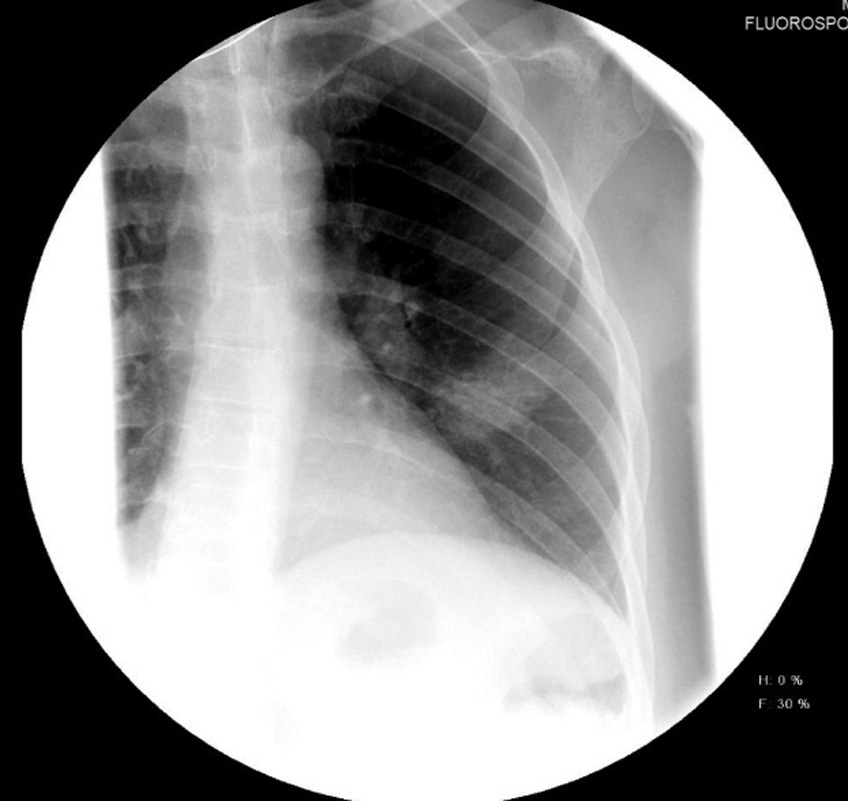

Рис. 1. Рентгенограмма органов грудной клетки до начала лечения препаратом бовгиалуронидаза азоксимер

Fig. 1. Chest X-ray imaging before treatment with Longidaza

На обзорной рентгенограмме грудной клетки: левосторонняя пневмония основания легкого. На амбулаторном этапе лечения на фоне проводимой противовирусной терапии назначен дексаметазон внутримышечно (в/м) 2 р/день на протяжении 1 нед по схеме. В последующую неделю отмечалось ухудшение состояния, появился ночной профузный пот; повышение температуры до 39,3 °С и снижение сатурации кислорода (SpO2) до 87 %. Снижение температуры при приеме жаропонижающих средств отмечалось на несколько часов с дальнейшим значительным повышением. Отмечено нарастание симптомов интоксикации.

На обзорной рентгенограмме грудной клетки: усиление легочного рисунка, двусторонняя пневмония (в средних и нижних отделах легких).

На цифровых обзорных рентгенограммах органов грудной клетки в прямой проекции отмечается положительная динамика за счет уменьшения в объеме и интенсивности участков консолидации паренхимы по легочным полям с обеих сторон. При выписке из стационара в удовлетворительном состоянии: SpO2 94 %, температура тела 36,0 °С, одышка — только на фоне незначительной физической нагрузки, гипервентиляционный синдром, сильная астения, сухой непродуктивный кашель.